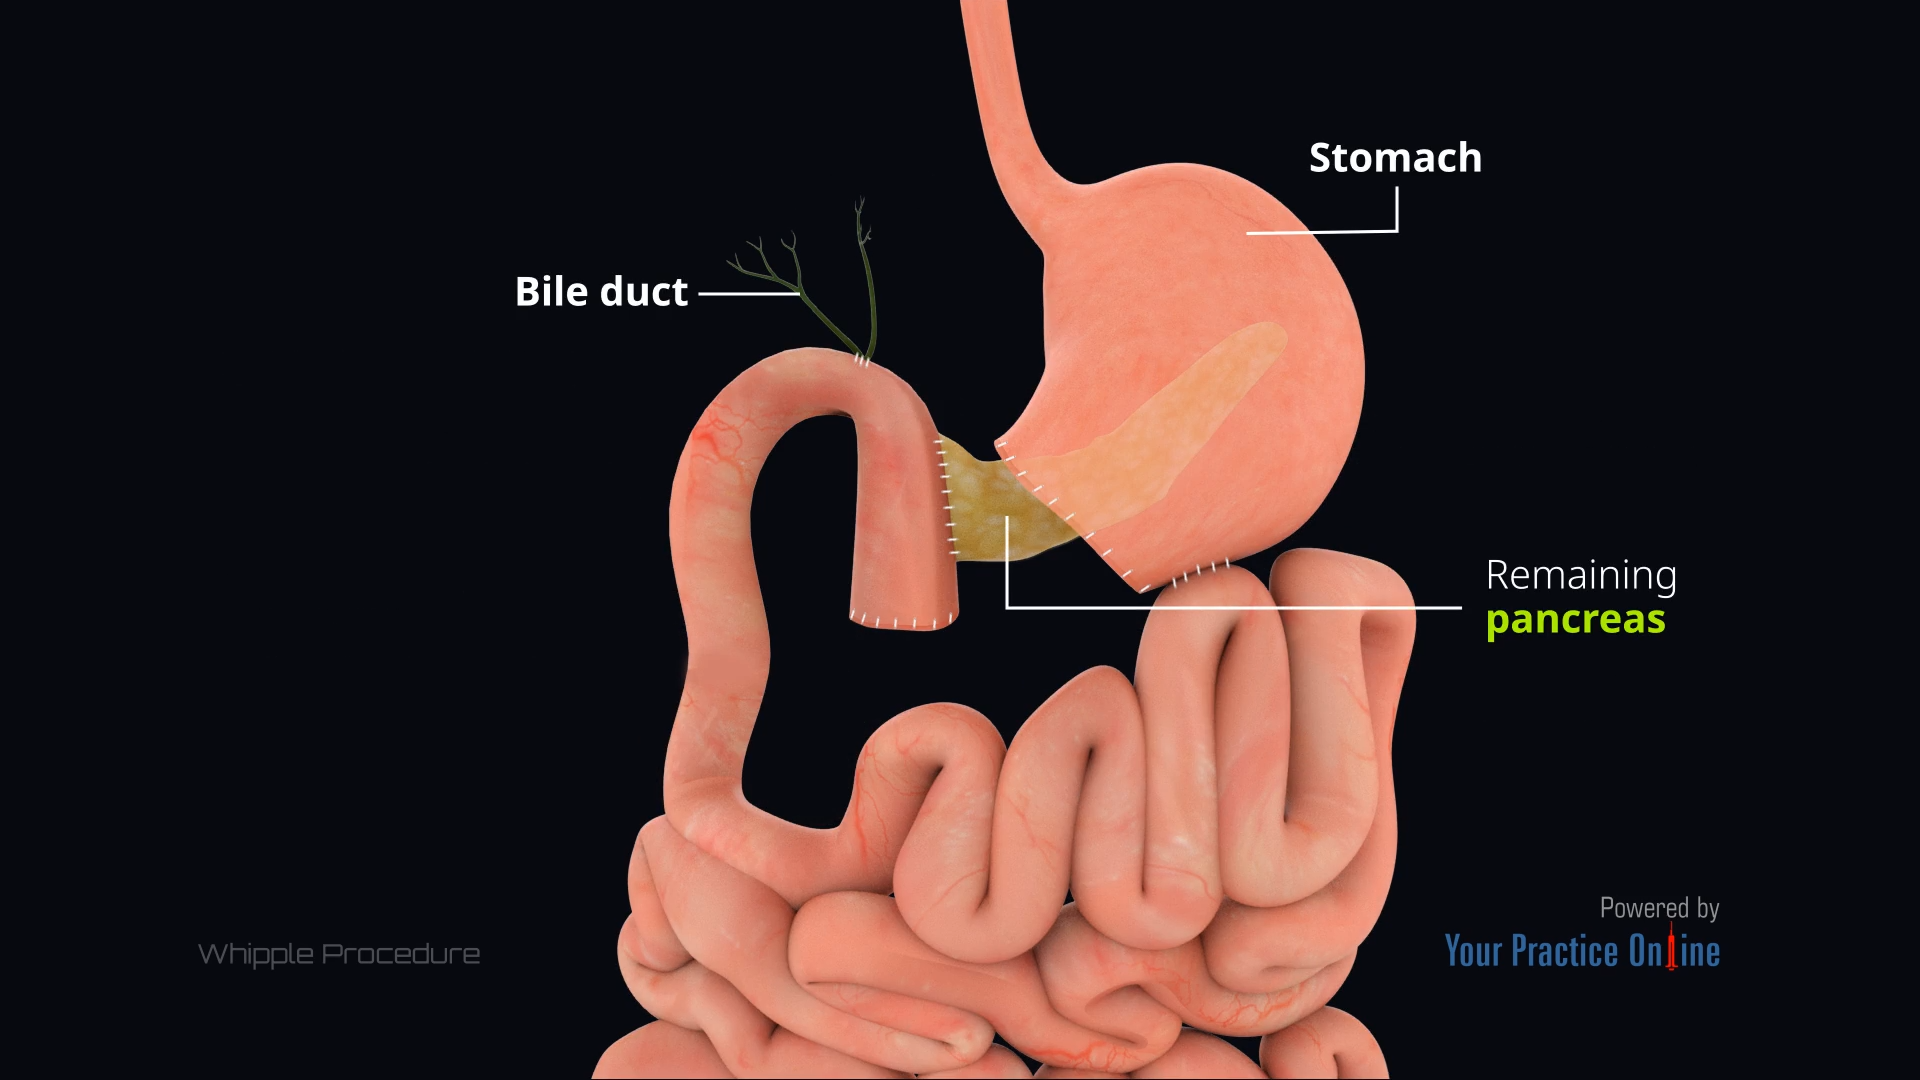

Whipple Procedure Animation

Whipple Procedure Animation

Whipple Procedure Animation

Whipple Procedure Animation